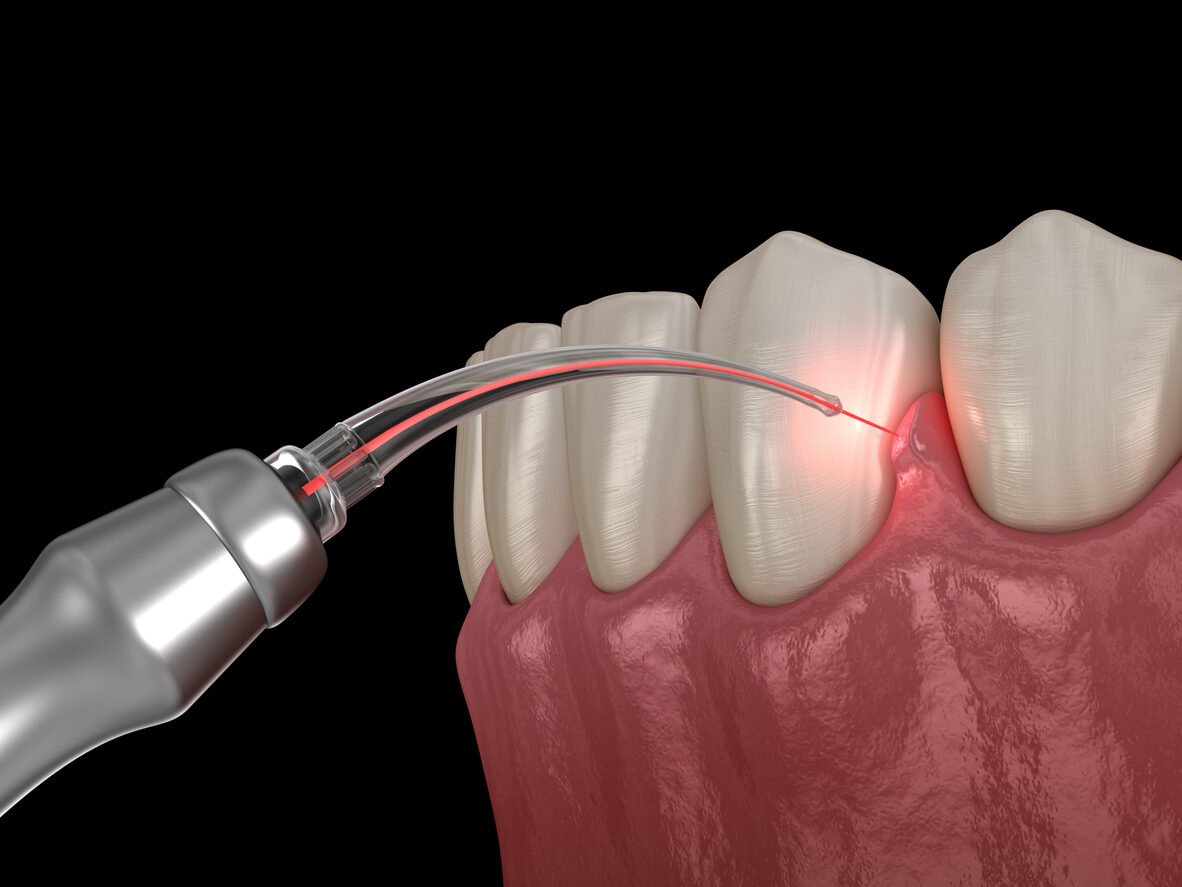

DirectionsFor use checking damaging progress of Perodontal disease.Also for use to treat Acute Ulcerative Gingivitis.

TREATMENT AND ARREST OF PERIODONTAL DISEASE

ultrasonic cleaning of pockets. clear pocket debris with Gingi-Fiz fill perio pocket Gingi-Sept regular professional care

| 3-5mm with bleeding:early established perio | ultrasonic cleaning of pockets.

1st visit: clear pocket debris with Gingi-Fiz fill perio pocket Gingi-Sept for 1 week. 2nd visit: clear pocket debris with Gingi-Fiz fill perio pocket Gingi-M for 1 week review repeat if not resolved: clear pocket debris with Gingi-Fiz fill perio pocket Gingi-Sept for 1 week. regular professional care

| 5-7mm with bleeding:soft and hard tissue damage, as well as bone loss | ultrasonic cleaning of pockets.

1st visit: clear pocket debris with Gingi-Fiz fill perio pocket Gingi-Sept for 1 week. 2nd visit: clear pocket debris with Gingi-Fiz fill perio pocket Gingi-M for 1 week review repeat if not resolved: clear pocket debris with Gingi-Fiz fill perio pocket Gingi-Sept for 1 week. regular professional care review and repeat every 3 months. Professional care